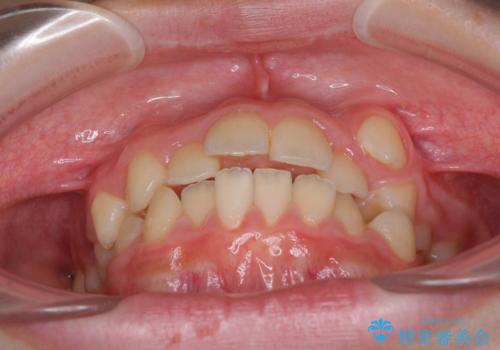

- 八重歯と乳歯が残っていることを気にして来院された患者様です。

乳歯が3歯残っており、下顎は左右ともに後続永久歯がない状態でした。

口元が突出しており、口が閉じにくかったため、乳歯を含め上下5歯を抜歯して矯正治療を行うこととしました。